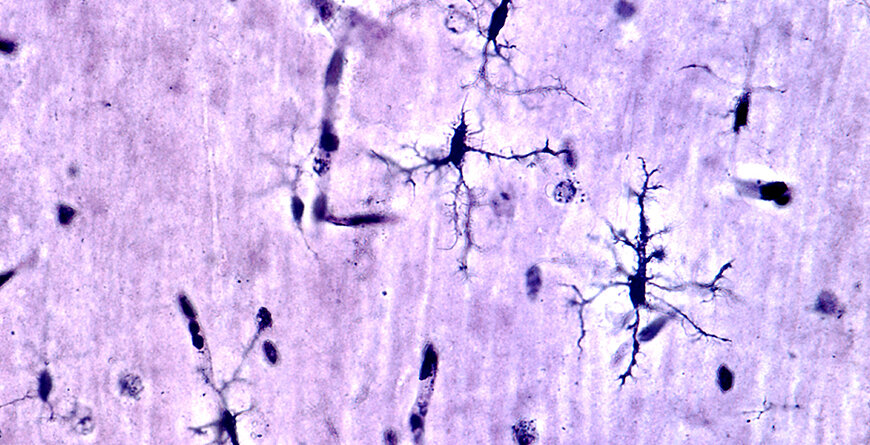

Curiosamente, gli effetti benefici della supplementazione permanente di colina riducono l’attivazione della microglia, cellule specializzate che liberano il cervello da detriti deleteri. Queste cellule lavorano naturalmente per mantenere il cervello sano, tuttavia, se sono iperattive causano infiammazione cerebrale e morte neuronale, sintomi comuni dell’alzheimer.

Le riduzioni osservate nella microglia associata a malattia, che sono presenti in varie malattie neurodegenerative, offrono nuove entusiasmanti vie di ricerca e suggeriscono diversi modi di trattare una vasta gamma di disturbi, tra cui lesioni cerebrali traumatiche, sclerosi multipla e morbo di Parkinson.

In secondo luogo, l’integrazione di colina riduce l’attivazione della microglia. L’eccessiva attivazione della microglia provoca infiammazione cerebrale e può eventualmente portare alla morte neuronale, compromettendo così la funzione cognitiva. La supplementazione di colina riduce l’attivazione della microglia, offrendo ulteriore protezione dalle devastazioni dell’AD.

Meccanicamente, le riduzioni nell’attivazione della microglia sono guidate dall’alterazione di due recettori chiave, l’acetilcolina nicotinica alfa7 e il recettore Sigma-1. Un nuovo rapporto di quest’anno ha scoperto che la colina può agire come agonista per i recettori Sigma-1. Questi risultati confermano che l’integrazione di colina per tutta la vita può alterare l’espressione del recettore Sigma-1, che in tal modo attenua l’attivazione della microglia. (Un agonista è una sostanza che attiva un determinato recettore.)

In questo studio, i ricercatori hanno utilizzato un labirinto d’acqua per determinare se i topi con sintomi simili all’AD che hanno ricevuto colina supplementare per tutta la vita hanno mostrato miglioramenti nella memoria spaziale. È stato scoperto che questo era effettivamente il caso, e il successivo esame del tessuto del topo estratto dall’ippocampo, una regione del cervello nota per svolgere un ruolo centrale nella formazione della memoria, ha confermato i cambiamenti nella beta-amiloide tossica e le riduzioni nell’attivazione della microglia.

A causa delle alterazioni dei principali recettori della microglia indotti dalla colina, i miglioramenti nel comportamento possono essere attribuiti alla ridotta attivazione della microglia. “Abbiamo scoperto che l’integrazione di colina per tutta la vita ha alterato l’acetilcolina alfa7 nicotinica e il recettore Sigma-1, il che potrebbe aver portato alla riduzione della microglia attivata associata alla malattia”, ha detto Velazquez.

Questi recettori regolano la risposta immunitaria del SNC e la loro disregolazione contribuisce alla patogenesi dell’AD.